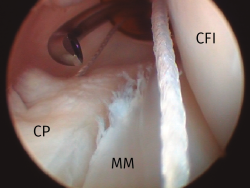

Figura 3. Reparación de una lesión de la rampa posterior del menisco interno, rodilla derecha. Uso de un portal posteromedial con una cánula de trabajo. Visión transescotadura. CFI: cóndilo femoral interno; CP: cápsula posterior; MM: muro meniscal.